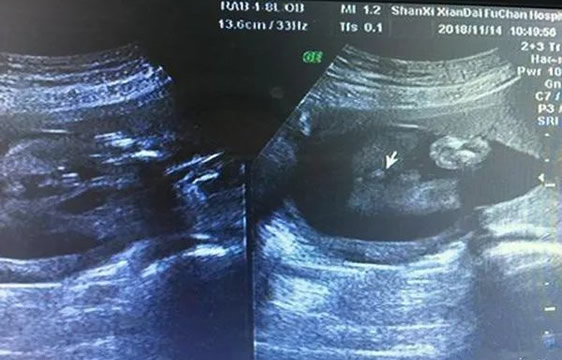

四维彩超检查报告单

已生了女宝的四维单子图像